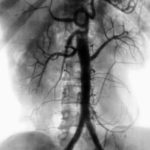

Найбільш інформативним способом діагностування вазоренальної АГ вважається ангіографія. Це процедура виконується в судинних центрах, з її допомогою можна виявити фактори розвитку стенотического процесу, оцінити локалізацію і ступінь стенозу.

Більш того, застосовуються скринінгові та малоінвазивні дослідження, що допомагають побачити ураження ниркових артерій і встановити показання до ангіографії або уникнути її при іншому генезі гіпертонії.

Так, висока чутливість відзначається при КТ-ангіографії, сцинтиграфія нирок із застосуванням інгібіторів АПФ, магніторезонансної ангіографії та дуплексному скануванні. Їх комбінують або застосовують окремо, що дає змогу провести адекватний скринінг до рентгеноконтрастної ангіографії.